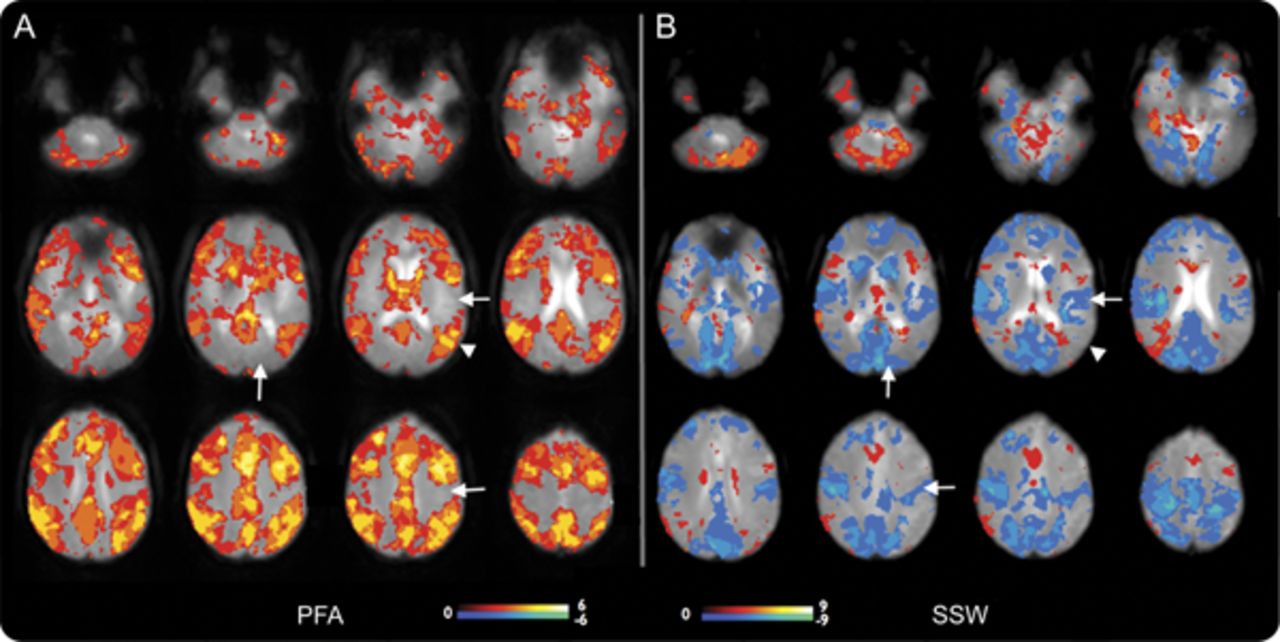

在所有患者6 PFA,皮质大胆的改变几乎完全是积极的信号。外显率的分布地图显示激活(图2一个;个案如图e 1上首页®网站www.首页neurology.org)。PFA-related大胆的增加主要影响广泛的额叶皮质“协会”地区,顶叶枕叶和颞叶,但似乎并没有意识到涉及初级皮层。

结合阈值SPM PFA的“外显率地图”(A)和(B)西南偏南约显示大脑皮层和皮层下的整体模式的激活和解除激活这些癫痫样的事件。颜色代表对象的数量规模与显著激活体素(黄色高于阈值的像素点为所有6科目PFA和9 f)。增加在大胆的信号显示在暖色和冷色的减少。没有大胆的反应主要在PFA皮质;初级运动、视觉和听觉皮层(箭头)没有激活或不激活体素,而所有这些领域显示减少大胆在f(同样的箭头在B)。在联合皮质(例如,箭头在顶叶皮层)强烈激活在量和没有大胆的在量的变化。这是真的协会地区除了一些地区的额叶皮质显示量的失活。皮层下结构,如脑干和尾状,显示激活量在PFA和失活。尽管个人更多的变化结果与量覆盖所有情况下导致这种识别的模式。大胆=血氧等级相关;PFA =阵发性快速活动; SPM = Statistical Parametric Mapping; SSW = slow spike and wave.

在5 6 PFA的数据集,有大胆的信号增加丘脑。大胆的信号增加尾状核和基底神经节也观察到在5 6例。单边模式时或者有单侧性的强调,PFA和大胆的信号变化的偏侧性与解剖病变,和最大的一侧丘脑参与与最大的一侧皮质的变化。

脑干显示增加大胆信号subcollicular水平与PFA的4 6例。小脑激活被认为在大多数主题(5 6)。

缓慢的上升和波。

量排放记录9例。他们与正面和负面的皮质大胆的混合信号的变化(图2、e 1和飞行)。

不像PFA,皮质是西南偏南约模式变量(图飞行)。的一部分,这可能是由于有限的数据量(患者9、10、13)。患者6,7,8弱难以解释的激活。患者1、2和5有强烈激活外显率最佳解释的引用映射(图2)。这表明失活往往是在初级皮质(电动机、视觉和听觉)和中线顶叶皮层。有分散在其他领域积极激活皮层,特别是额叶皮层的某些地区。

大胆的信号变化4例患者出现丘脑在场。这些都是双边积极2(病人1和5),双边-在一个病人(6),和积极的一面和消极变化在另一个病人(2)。

有4例患者出现大胆的尾状核的活动减少,这是外显率的地图(图2)。脑干显示大胆的信号变化subcollicular水平4例(2增加和减少2)。